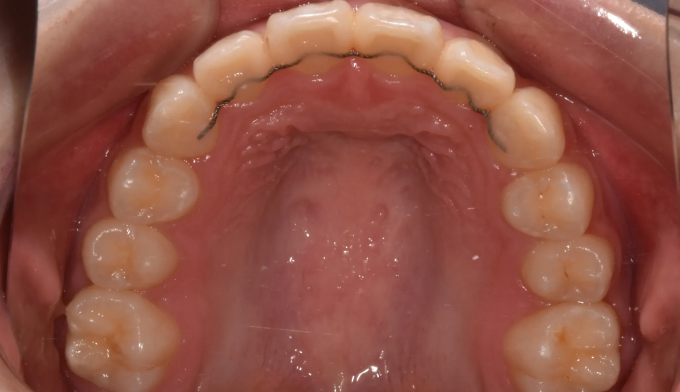

위턱, 아래턱 모두 치아 배열 공간이 부족한 경우 입니다.

확장장치를 이용해 공간 부족을 해결하고 치열을 배열하면 간단히 끝낼 수 있습니다.

이때 입술의 두께나 위치, 위아래 앞니의 각도를 종합적으로 고려하여야 합니다.

치아를 배열한다고 앞니가 뻐드러지면 잘못된 교정치료입니다.

총 치료기간은 20개월 소요되었습니다.